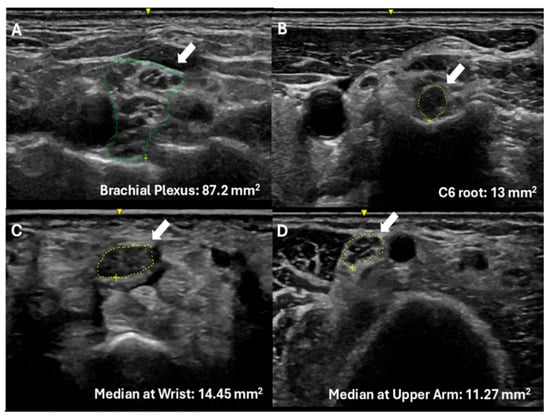

Improved Clinical and Radiological Outcomes with Double-Cage Biportal Endoscopic Transforaminal Lumbar Interbody Fusion: A Comparative CT-Based Study

by Yu-Hao Huang and Jwo-Luen Pao

Diagnostics 2025, 15(20), 2652; https://doi.org/10.3390/diagnostics15202652 - 21 Oct 2025

Cited by 1 | Viewed by 1504

Abstract

Background/Objectives: When transitioning from an older surgical technique to a newer one, we expect improved treatment outcomes and fewer complications. However, direct comparative studies to confirm these advantages are often lacking. Tubular minimally invasive transforaminal lumbar interbody fusion (MISTLIF) has been widely [...] Read more.

Background/Objectives: When transitioning from an older surgical technique to a newer one, we expect improved treatment outcomes and fewer complications. However, direct comparative studies to confirm these advantages are often lacking. Tubular minimally invasive transforaminal lumbar interbody fusion (MISTLIF) has been widely used, but limitations in visualization and endplate preparation may compromise fusion quality. Biportal endoscopic TLIF (BETLIF), a more recent alternative, offers enhanced magnification and superior hemostasis. Still, CT-based comparative data on fusion integrity remain limited. To evaluate the clinical and radiological outcomes following a chronological transition from MISTLIF to BETLIF, using thin-slice CT to assess fusion integrity. Methods: This retrospective study analyzed 179 patients treated by a single surgeon between January 2018 and May 2021. The first 90 cases underwent MISTLIF, followed by 89 BETLIF procedures. Clinical outcomes included Visual Analog Scale (VAS), Oswestry Disability Index (ODI), and Japanese Orthopedic Association (JOA) scores. Radiological assessments at one year postoperatively (X-ray and thin-slice CT) included disc height, segmental lordosis, Bridwell fusion grade, cage subsidence, and subchondral osteolysis. Results: BETLIF was associated with significantly shorter hospital stays (5.7 vs. 7.4 days) and fewer transfusions (0% vs. 14.7%). BETLIF showed significantly better ODI (12.7 vs. 23.5), JOA scores (26.4 vs. 20.6), and comparable VAS improvement. Radiologically, BETLIF had significantly higher fusion rates (93.3% vs. 82.4%), greater disc height restoration, and lower rates of cage subsidence (5.0% vs. 13.7%) and osteolysis (13.3% vs. 52.9%). Conclusions: BETLIF demonstrated superior clinical and radiological outcomes, likely due to enhanced endoscopic visualization and precise endplate preparation. Full article

(This article belongs to the Special Issue Diagnosis and Management of Spinal Diseases)

Show Figures

Figure 1